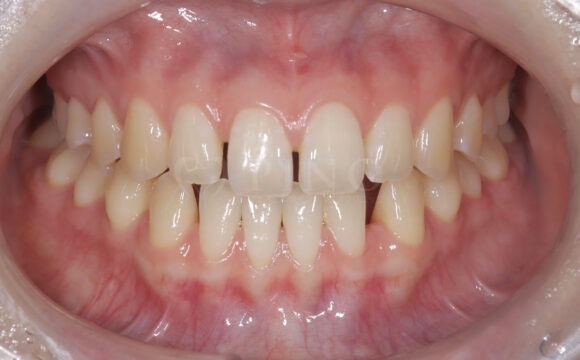

症例3:ワイヤー矯正後の後戻りが気になる(40代女性)

主訴 ワイヤー矯正後の後戻りが気になる 診断名 叢生 治療方法 マウスピース部分矯正 抜歯 なし オルソパルス なし 治療期間 9ヶ月 費用 436,000円 副作用・注意点 矯正後の後戻りを防ぐためリテーナーの使用が必要となる 備考 奥歯に噛み合わせ不良がない場合、部分矯正が適応となる -